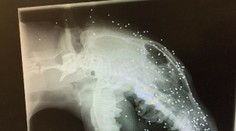

Turecko V Turecku strelili psíka do tváre brokovnicou, v lebke a koži má až 50 brokov radoslav kozak 24. 1. 2017